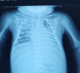

Diagnostic assessment: the cerebral computed tomography (CT) scan (Figure 1) showed the presence at the level of tubular hyperdensity subarachnoid well-limited spaces, realizing the "cord sign" harmonious with a thrombus of the cortical veins, associated with bilateral hypodense foci with a hemorrhagic component. The set of these lesions was associated with edematous infiltration of soft tissues of the left parietal scalp related to a hematoma in the process of liquefaction. The chest X-ray (Figure 2) demonstrated a bilateral alveolo-interstitial syndrome. The complete blood count showed a microcytic hypochromic anemia at 4.9g/l, a leucopenia at 3,900/ul; a neutropenia at 1000, a lymphopenia at 1000, and thrombocytopenia at 107.000/ul. The CRP at 116 mg/l, a TP at 23%, TCK: 43 sec, ALT 779 IU/L, AST 500 IU/L, albuminemia: 27 g/L, urea 7.52 mmol/L, and creatinine: 31.82 ùmol/L. The hemoculture remained sterile, whereas the cytobacteriological study of sputum isolated a Klebsiella pneumoniae. Facing the seriousness of the clinical picture associated with the pancytopenia, the persistent lymphopenia, and the hepatocellular insufficiency, a rapid HIV test was positive. The viral load was 2,760,000 copies/ml, confirming the infection by the human immunodeficiency virus.

Figure 2: presence at the level of the bilateral frontal subarachnoid spaces and in the right temporo-occipital of well-limited tubular hyperdensities realizing the "cord sign": harmonious aspect with a thrombus of the cortical veins, associated with bilateral hypodense foci presenting a hemorrhagic component: secondary infarction to thrombosis